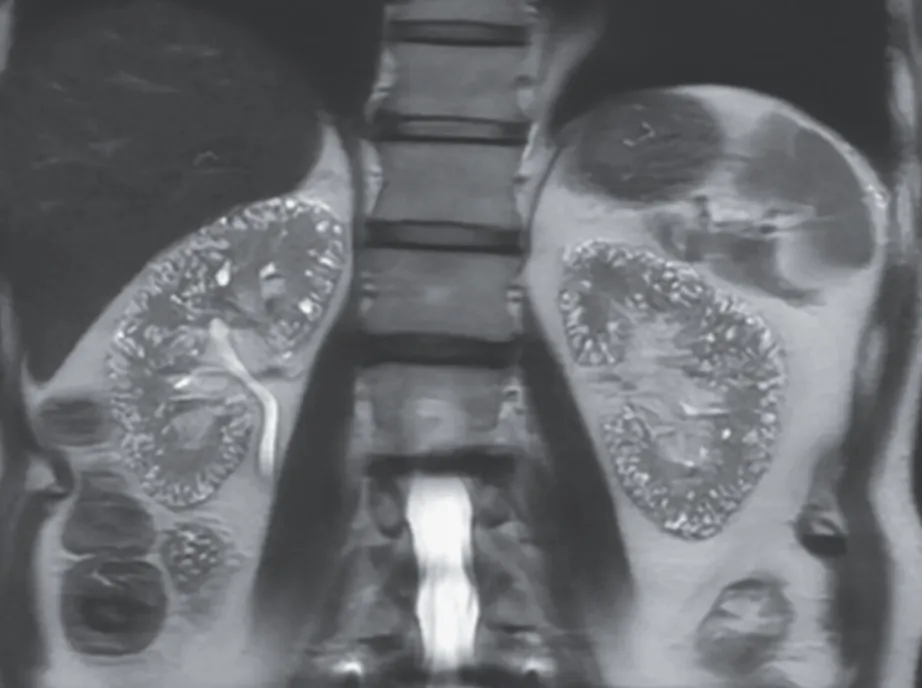

Os achados da TC sem contraste revelaram rins aumentados de tamanho, múltiplos cistos renais e nefrocalcinose (Figura 1).

A síndrome de Beckwith-Wiedemann é uma das causas do rim espongiomedular, que se apresenta comachados específicos na tomografia computadorizada, incluindo nefrocalcinose medular, dilatação cística e um padrão de estrias semelhantes a buquês de flores nas papilas renais.